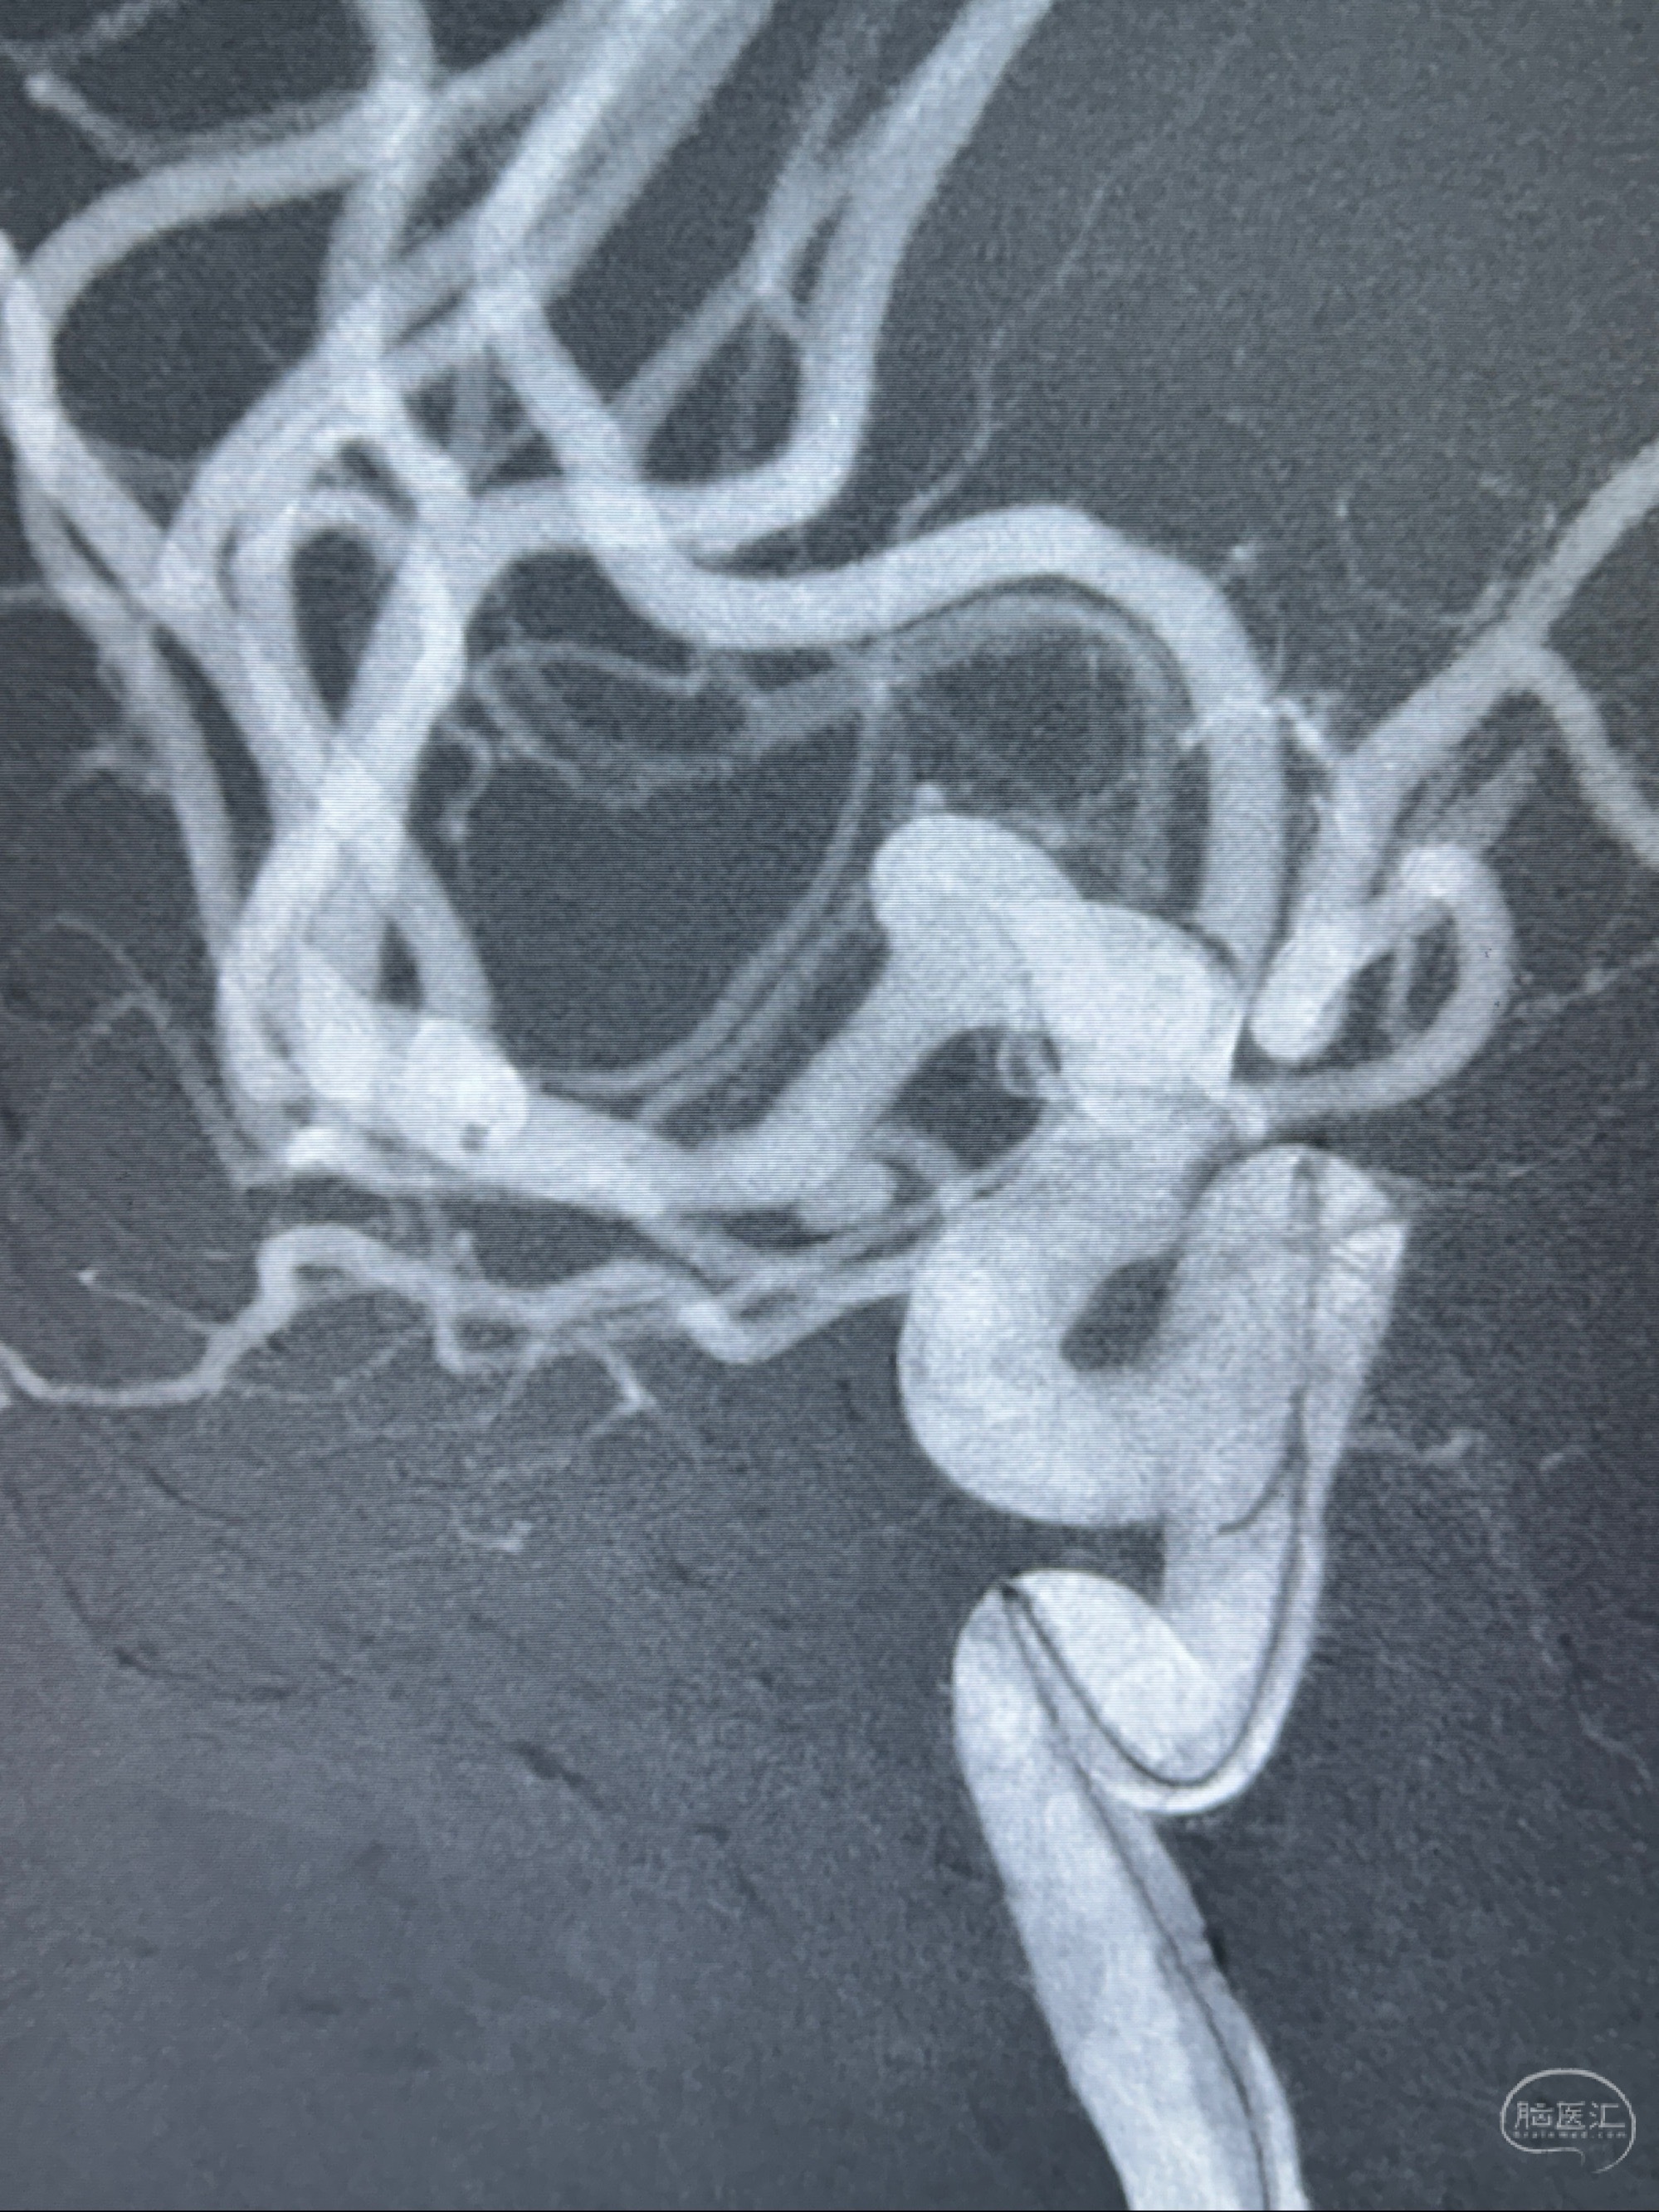

2023-11-24DSA:右侧大脑中动脉下干起始部动脉瘤,约2.3*2.5mm,形态规则

治疗策略:

- 随访?

- 夹闭?

- 单弹簧圈填塞?

- 支架辅助治疗?